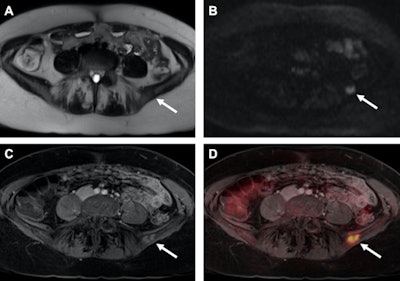

Images are from the January 2017 study of a patient with recurrent breast cancer and a PET-positive bone metastasis of the left iliac wing, which can be identified on T2-weighted half-Fourier acquisition single-shot turbo spin-echo (HASTE) (A) as well as on diffusion-weighted imaging (DWI) (B, arrows). The identical tumor lesion shows moderate contrast-enhancement on T1-weighted volumetric interpolated breath-hold examination (VIBE) images (C) and can be detected with a higher conspicuity after image fusion on PET/MRI (D). All images courtesy of Dr. Johannes Grueneisen.Study logistics